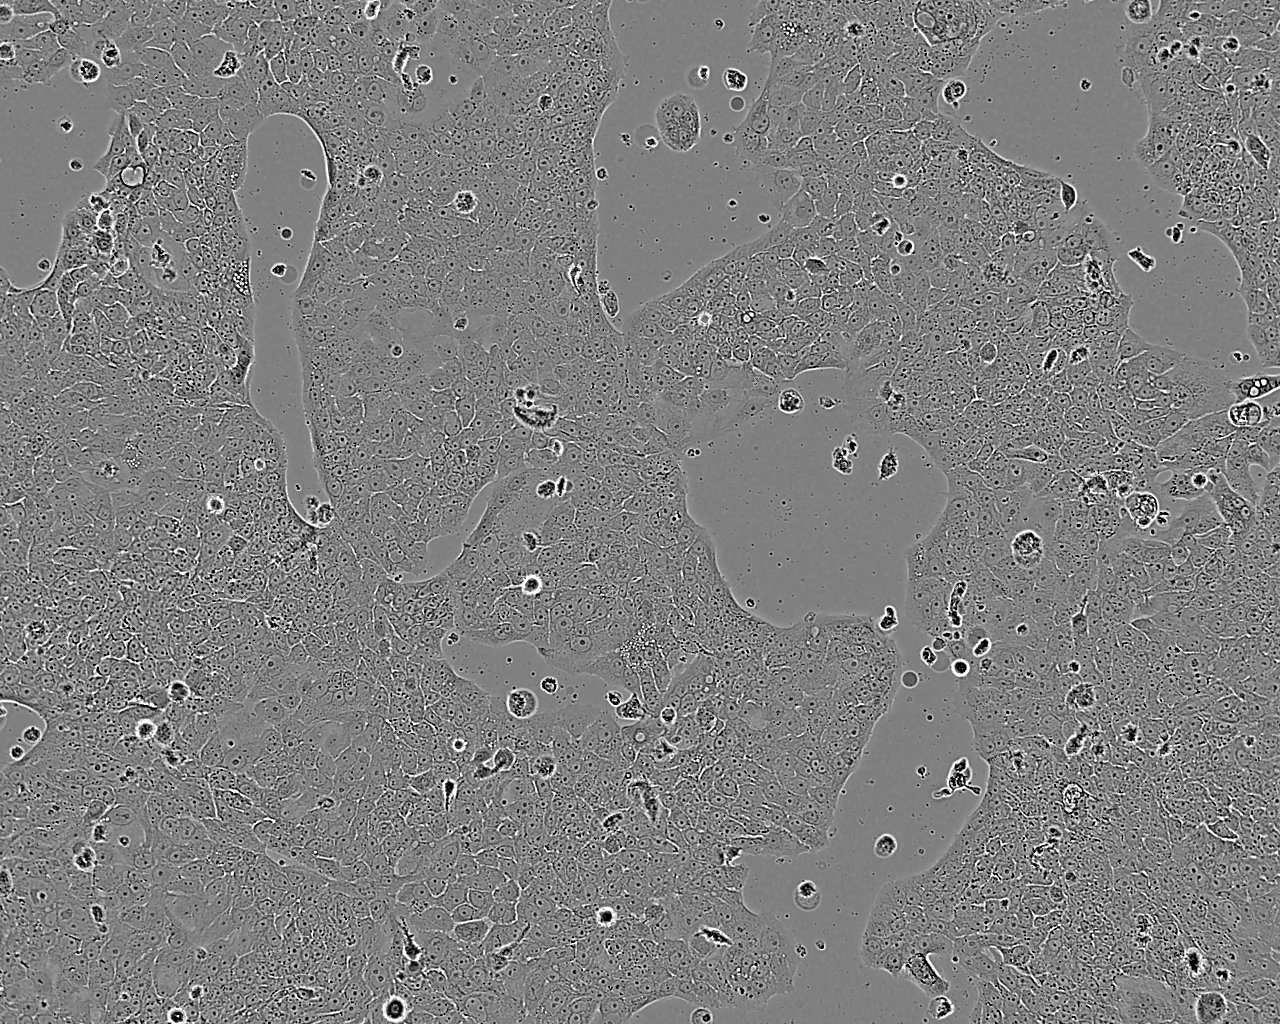

Cells grow as small dense islands and will not form a monolayer. Split cells 1:3 to 1:6 i.e. seeding at 2-4 x 10,000 cells/cm² using 0.05% trypsin or trypsin/EDTA. After thawing, the 1st subculture interval may take up to 14 days. Medium change after 4 days.

Images